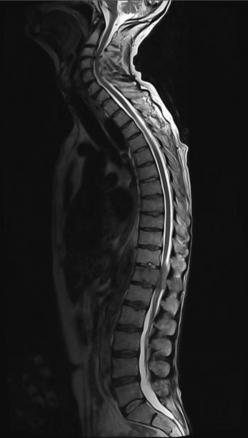

Métastase T12 hétérogène en T2, avec recul du mur postérieur et compression du cordon médullaire.